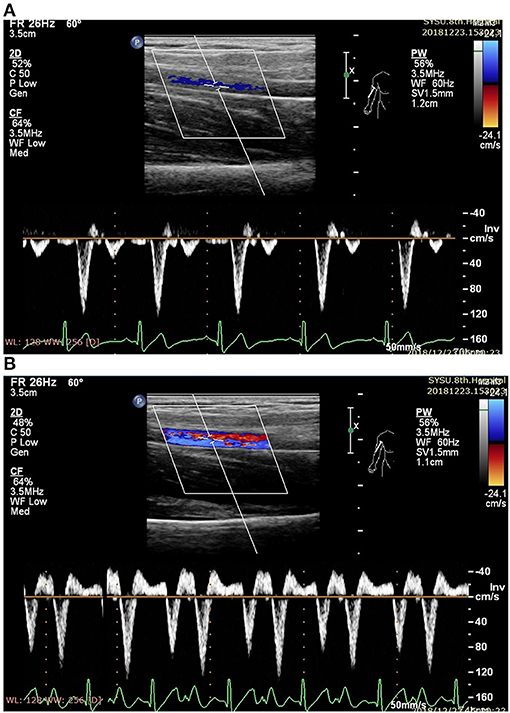

The ultrasound picture and Doppler spectrum of carotid and brachial arteries during EECP are presented in Figures 1, 2, respectively. The effect of EECP on the measured variables varied in each artery as did the differences between the patients with CAD and controls are illustrated in Figures 37. In addition, the significant differences in the hemodynamic parameters in females and males of both groups were analyzed by subgroup analysis. These results are shown in Table 2.

FIGURE 1

www.frontiersin.org

Figure 1. Measurement of blood flow velocity spectrum in the right common carotid artery (CCA) [A before enhanced external counterpulsation (EECP) and B during EECP].